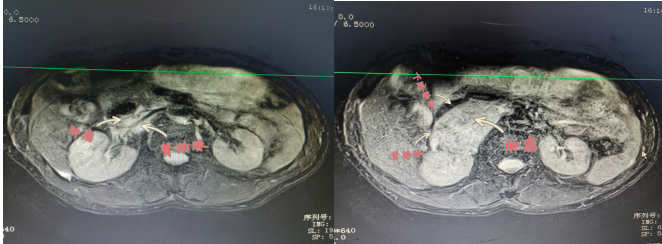

患者陽(yáng)某,67歲,8月2日因“反復(fù)胸悶氣促2年余,再發(fā)伴頭暈黑蒙3天?!本驮\于衡陽(yáng)市中心醫(yī)院心血管內(nèi)科,患者血壓波動(dòng)大,最高值199/118mmHg,最小值98/57mmHg,射血分?jǐn)?shù)最低42%;完善相關(guān)檢查發(fā)現(xiàn)右腎上腺巨大腫物,大小約57×73×75mm,遂轉(zhuǎn)入衡陽(yáng)市中心醫(yī)院泌尿外科治療,泌尿外科醫(yī)護(hù)團(tuán)隊(duì)前期做了充分的準(zhǔn)備,并進(jìn)行科內(nèi)討論,麻醉科、心血管內(nèi)科專(zhuān)家會(huì)診,充分予以穩(wěn)定血壓、心率和擴(kuò)容等術(shù)前處理。

2022年9月15日,醫(yī)院為患者行腹腔鏡下右側(cè)腎上腺瘤腫瘤切除術(shù),術(shù)中,患者右側(cè)腎上腺腫瘤于腎門(mén),壓迫下腔靜脈,右腎靜脈移位,包繞右腎動(dòng)脈。腫瘤體積大,血運(yùn)豐富與周?chē)M織邊界不清, 與大血管粘連,手術(shù)風(fēng)險(xiǎn)極大,術(shù)中鉗夾,擠壓腎上腺瘤體導(dǎo)致腎上腺激素釋放,手術(shù)中血壓的急劇變化。充分顯露手術(shù)視野,仔細(xì)、輕柔操作對(duì)腫瘤切除十分關(guān)鍵。麻醉科主任譚滇湘全程護(hù)航。由于準(zhǔn)備充分、配合到位,雖術(shù)中情況多變,最終手術(shù)成功。術(shù)后病檢結(jié)果顯示腫瘤完整切除。患者術(shù)后恢復(fù)良好,于2022年9月24康復(fù)出院。